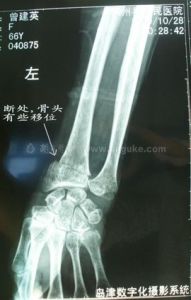

手腕骨折在日常生活中較為常見,受傷者中以老年人居多,大部分患者是因為跌倒後手掌著地所致。骨折多發生在橈骨遠端近關節2cm處,臨床上稱為柯力氏骨折。如未得到及時有效的治療,患者腕關節將遺有關節畸形、關節活動功能受限,以及關節疼痛等症狀,常給患者的日常生活帶來諸多不便。因此,診治時必須做到正確的復位、良好的固定。